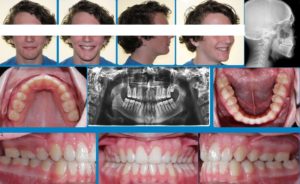

A 12 year old Caucasian male presents with a chief concern that “I don’t like my overbite”